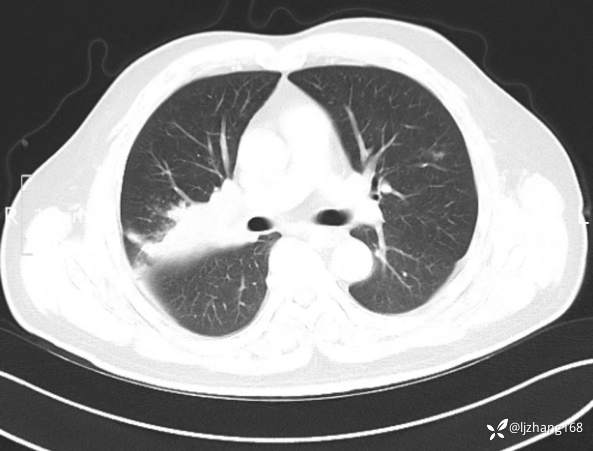

中年男患,右肺团片影,炎症0R肿瘤?

辅助检查:糖化血红蛋白12.3%。肺炎支原体IgG、IgM、呼吸道合胞病毒均未见明显异常。胸部CT:右肺上叶阻塞性肺炎。